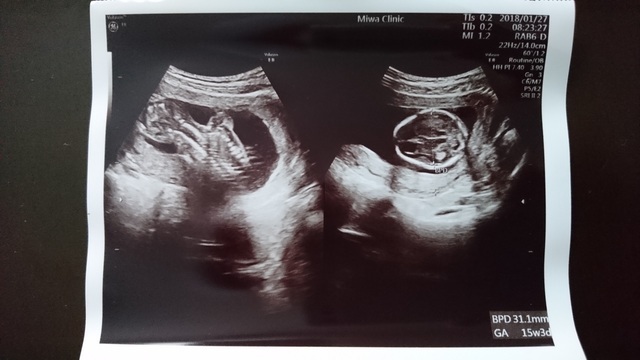

11週0日(11w0d・女の子)|pon2019610 さん(28歳)

エコー写真撮影時のエピソード:

妊娠が分かった産婦人科ではお産ができないため、紹介された産院で初めてのエコーでした。

前回も前々回も流産しており、不安な気持ちいっぱいで産院に向かってしてもらったエコー。

私の不安をよそに、まるで私を安心させるようにいっぱい動いてくれた赤ちゃん。エコーをする先生も笑っておられました。

あまりに動き回るものだから写真におさめるタイミングも大変だったみたいで、いただいた写真を改めて見返すと、きっとぶれてしまったんだと思いますが、まるでくちばしがはえているかのように見える写真が!

おもわず主人と笑ってしまいました(笑)

私の家族に見せると、くちばしあるやん!くちばしっち(たまごっちのキャラ)や!と(笑)

おかげでそのときからお腹の子は『くっちー』と呼ばれています(笑)

産まれてからも私の家族からの呼び名がくっちーのままだったらどうしよう?と今から心配です(笑)